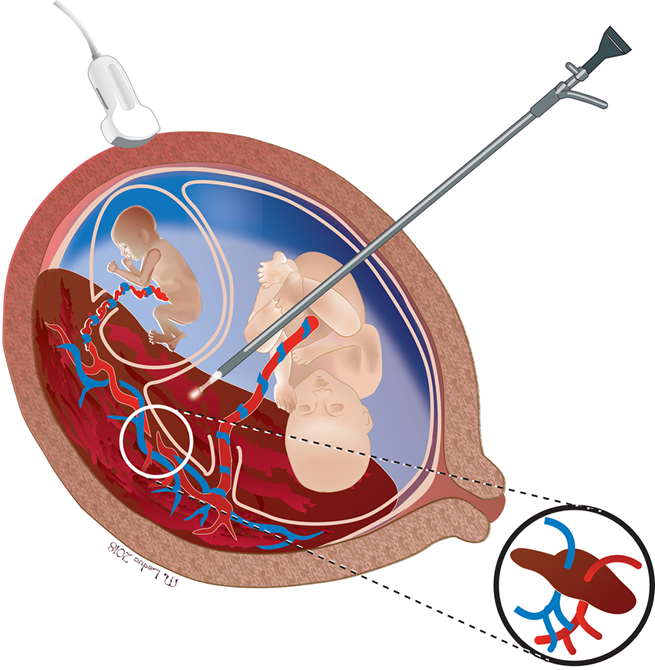

Comment peut-on traiter le syndrome transfuseur-transfusé?

Le STT est traité par la fœtoscopie laser, une chirurgie minimalement invasive où les anastomoses placentaires sont coagulées et le placenta est virtuellement séparé en deux. En même temps, le surplus de liquide chez le « receveur » est aussi drainé.

Cette procédure est effectuée par une seule incision de moins d’un cm par laquelle un trocart (tige cylindrique) est inséré. Elle se fait en salle opératoire, sous sédation et anesthésie locale. Cette procédure permet la survie d’un ou des 2 jumeaux dans 60-90% des cas.

Dans certains cas sévères, la fœtoscopie laser n’est pas possible techniquement ou non privilégiée, car le risque de décès ou séquelles neurologiques graves chez un jumeau est trop grand.

Dans ces cas, la réduction sélective par radiofréquence ou occlusion du cordon peuvent être effectués.

Fœtoscopie laser